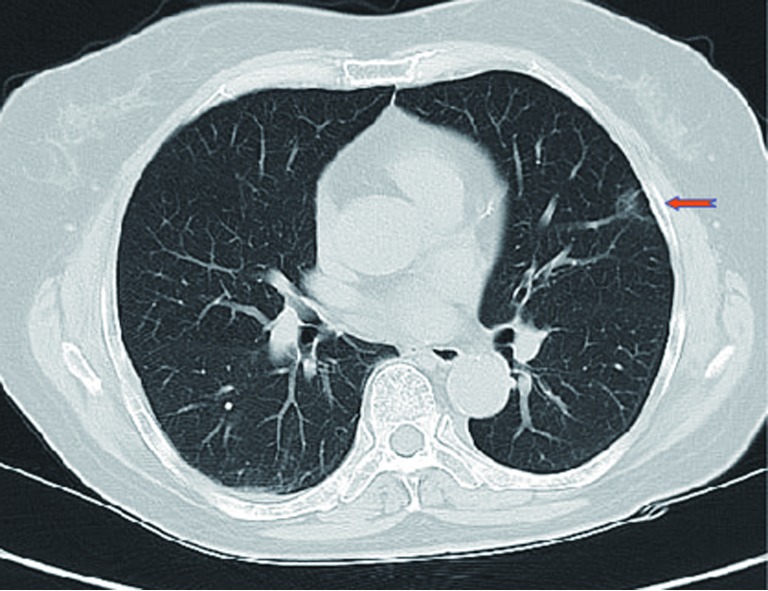

A 64-year-old female presented with a 2.0 cm × 2.0 cm × 1.0 cm nodule in posterior segment of right upper lobe and a ground glass opacity (GGO) in the left upper lobe on computed tomographic (CT) (Figures 1,2) was admitted in our institute on March 16th, 2014. The patient underwent preoperative staging and cardiac and pulmonary function assessment. PET-scan indicates no signs of metastasis. Under general anesthesia with double lumen tube, the patient underwent uniportal cVATS lobectomy for right upper lung tumor on March 19th, 2014 (Figure 3). The final pathologic TNM staging is T1aN0M0 (IA). Regular follow up was initiated for the GGO in the left upper lobe.

Figure 2.

A GGO in the left upper lobe. GGO, ground glass opacity.